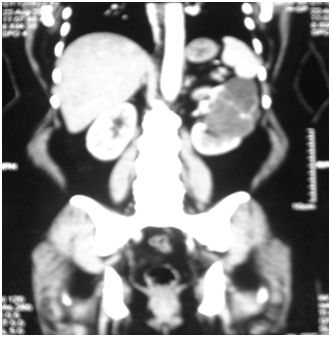

A 53years old obese woman presented with vague abdominal pain of one year duration. Physical examination was unremarkable. Ultra sonography of the whole abdomen detected an exophytic complex cystic lesion measuring about 10x8cm in upper pole of left kidney (Figure 1). MDCT whole abdomen showed 9.4x7.7x7.5cm sized multiloculated cystic lesion with enhancing septae and calcifications with solid nodular areas (Figure 2). The patient was diagnosed as Stage II left Renal Cell Carcinoma and subjected to Radical Nephrectomy. Adrenal was also removed as the tumor was in upper pole. On gross examination the tumour was multi nodular. Cut surface shows a spongy mass measuring 11x8.5x5cm, filled with yellowish serous fluid in the upper pole. On microscopic examination, the tumour was composed of variably sized tubules and fenestrated channels lined by bland cuboidal cells to epithelioid cells. No mitosis, cytological atypia, or nuclear pleomorphism was seen. Remaining kidney showed patchy chronic pyelonephritis with glomerulosclerosis and scarring. The adrenal showed normal histological appearance. Histopathology of the tumor was suggestive of Adenomatoid tumor of kidney (Figure 3). The tumor was positive for vimentin on immunohistochemistry.

Figure 2 Multiloculated cystic lesion with enhancing septae and calcifications with solid nodular areas.